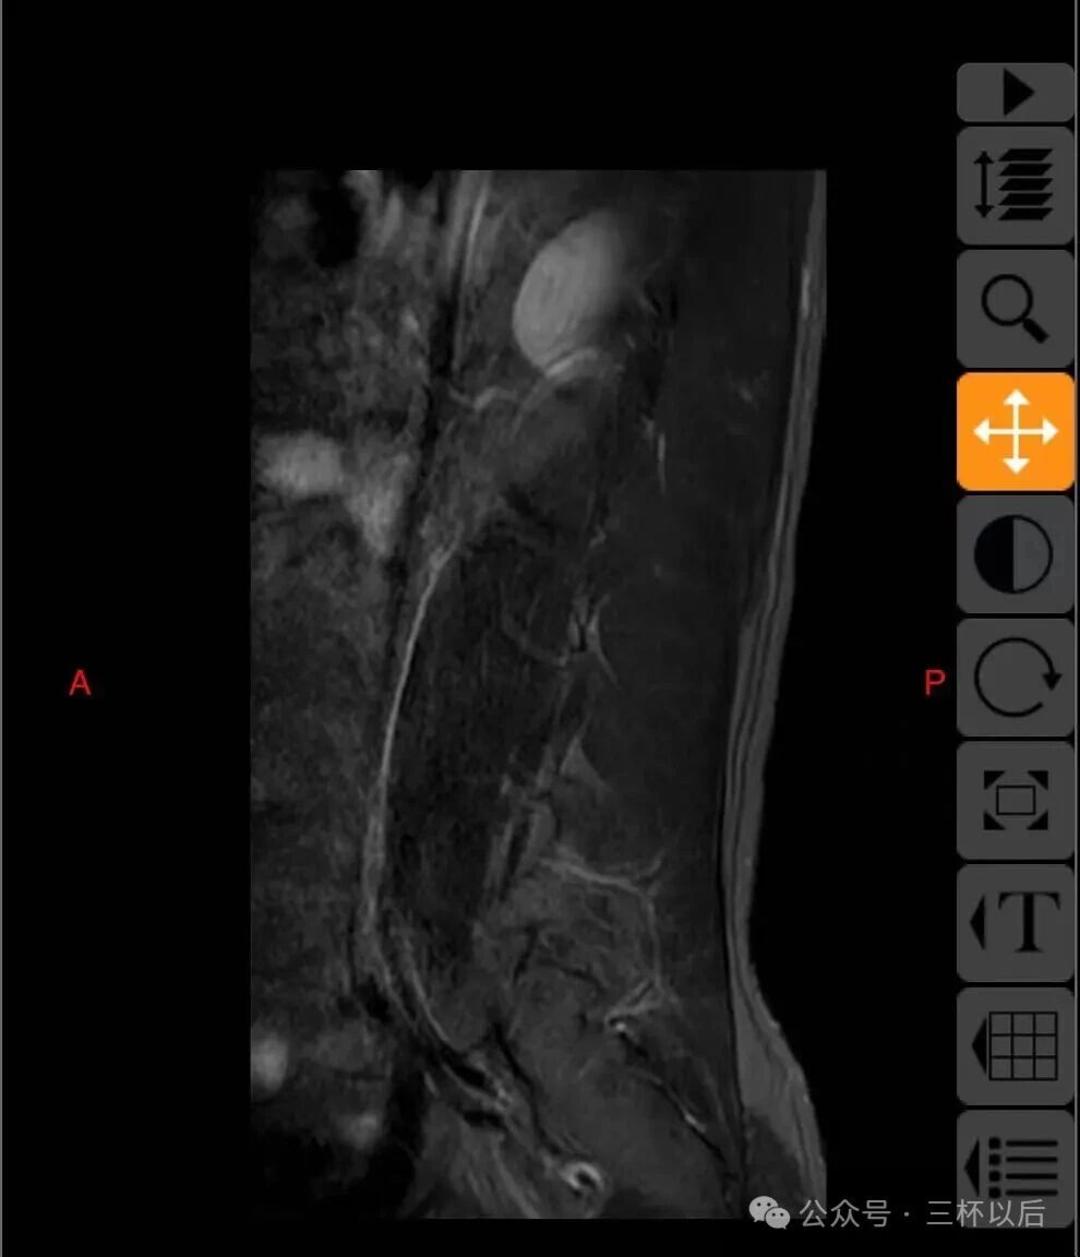

顺便贴一下拍的片子,如果有懂行的欢迎给我建议,我听劝的。真真希望能恢复如初,现在每天都能感受到疼痛,用了各种办法也不管用。